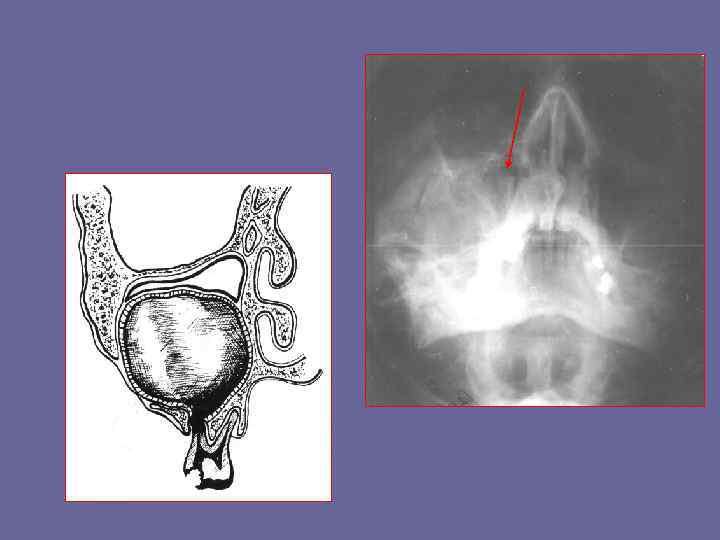

Опишите рентгенограмму

По мере рост кисты могут распространяться одновременно в сторону полости носа и в сторону верхнечелюстной пазухи